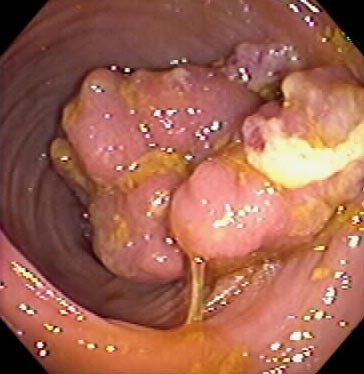

Πολύποδες του παχέως εντέρου: Οι πολύποδες είναι καλοήθεις όγκοι του παχέως εντέρου που είτε παρουσιάζονται ως μονήρεις βλάβες, είτε σπανιότερα στα πλαίσια κάποιου συνδρόμου (οικογενής πολυποδίαση, σύνδρομο Gardner, σύνδρομο Peutz-Jeghers). Ανατομικά ο πολύποδας είναι μια προσεκβολή του βλεννογόνου του εντέρου. Πιο συχνοί είναι οι αδενωματώδεις πολύποδες οι οποίοι πρέπει πάντα να αφαιρούνται και να εξετάζονται ιστολογικά. Κλινικά οι πολύποδες εκδηλώνονται με βλεννοαιματηρές κενώσεις, αίσθημα ατελούς αφόδευσης ή άλγος στην κάτω κοιλιά, πολύ συχνά όμως δεν δίνουν καθόλου συμπτώματα. Η διάγνωση τους τίθεται με βαριούχο υποκλυσμό ή καλύτερα με κολονοσκόπηση με την οποία συνήθως και αφαιρούνται. Εάν δεν είναι δυνατή η αφαίρεση τους με την κολονοσκόπηση, πρέπει να αφαιρούνται χειρουργικά διότι η πιθανότητα εξαλλαγής τους είναι μεγάλη. Η πλειοψηφία των καρκίνων του παχέως εντέρου αναπτύσσονται σε έδαφος αδενωματώδων πολύποδων. Μετά την αφαίρεση οι ασθενείς πρέπει να ελέγχονται ενδοσκοπικά σε τακτική βάση για την πιθανότητα υποτροπής τους.